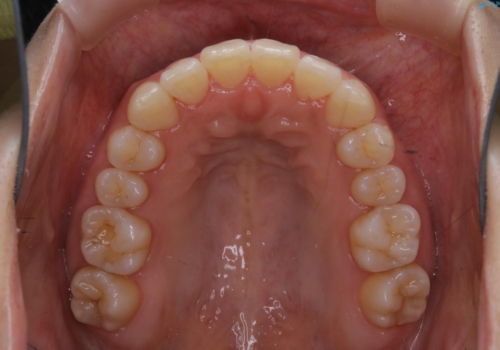

- 上下の前歯のがたつきが気になるとのことで来院されました。最短治療とインビザラインでの矯正治療をご希望されました。

前歯のがたつきを無くすためには、スペースを確保する必要があります。上の前歯のがたつきは軽度ながたつきのため、歯と歯の間を研磨をして、そのスペースを使い並べていきます。下の前歯は、1本前歯を抜いて研磨せずに、その抜歯したスペースを使い並べることになりました。

インビザライン・ライトにて矯正治療を行うことになりました。